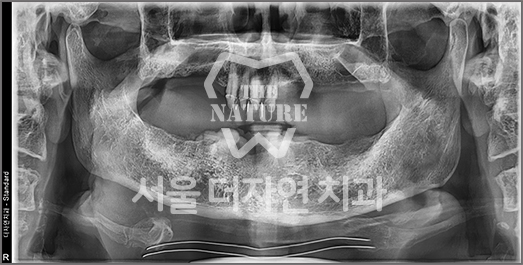

• BEFORE: 2021.11.02

• AFTER: 2022.01.19

An implant placed at another clinic was found to be significantly mispositioned,

requiring revision surgery to correct the placement to the proper position.

Implant Revision Surgery

Revision implant surgery is more challenging

and complex than the original procedure

Improper implant surgery or inadequate implant maintenance can lead to complications accompanied by pain. Implant revision surgery involves removing the existing implant, rebuilding the alveolar bone, reshaping the gingival contour,

and placing a new implant in the correct position.